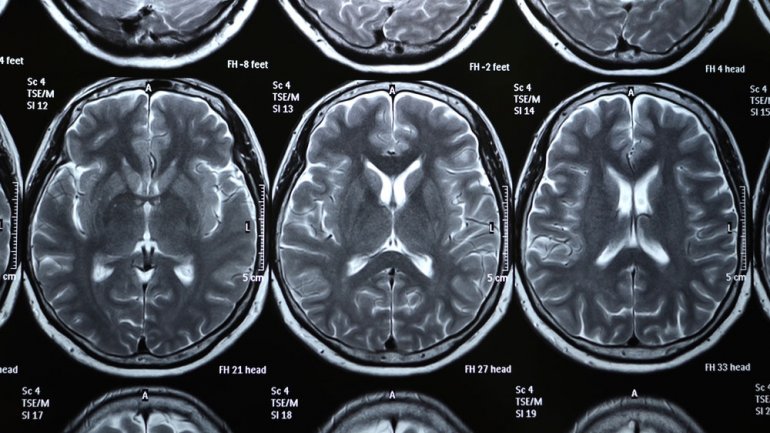

Among 831 patients treated in hospital emergency departments for concussion, or mild traumatic brain injury (TBI), only 44 percent saw a physician or other medical provider within three months, the scientists report. The study appeared in JAMA Network Open on May 25, 2018.

The researchers found that of those patients who saw a provider within three months, 15 percent visited a clinic that specialized in concussion or traumatic brain injuries, while approximately half saw a general practitioner, who may or may not have training in managing this condition. More worrisome was the finding that even among those concussion patients with more serious signs and symptoms, many had no further care after hospital discharge. Of the 236 patients whose CT scans indicated a lesion, and 279 patients with three or more moderate-to-severe post-concussive symptoms, 40 and 41 percent, respectively, did not see a physician or health provider within three months after discharge.